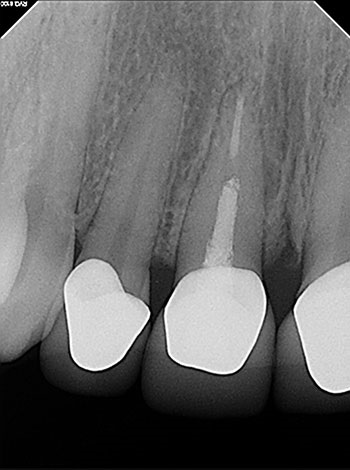

Case 5: Bilateral lesions

This patient was very worried that she was going to lose her front tooth, #8. Her dentist was concerned that the root had been split by a large, tapered post given the context of the bilateral radiolucencies located at the bottom of the post.

No crack was seen when the post was removed, nor were any lateral canals located. This tooth was treated in three visits over six months using a calcium hydroxide intracanal medicament. It is possible that a nidus of bacteria remained in the gap between the obturation and the post.

The patient’s symptoms resolved after the first visit. The case was obturated after confirming full bony healing. She is still extremely appreciative of the efforts made to save her front tooth.

Fig. 19: Preop PA.

Fig. 21: Recall PA.